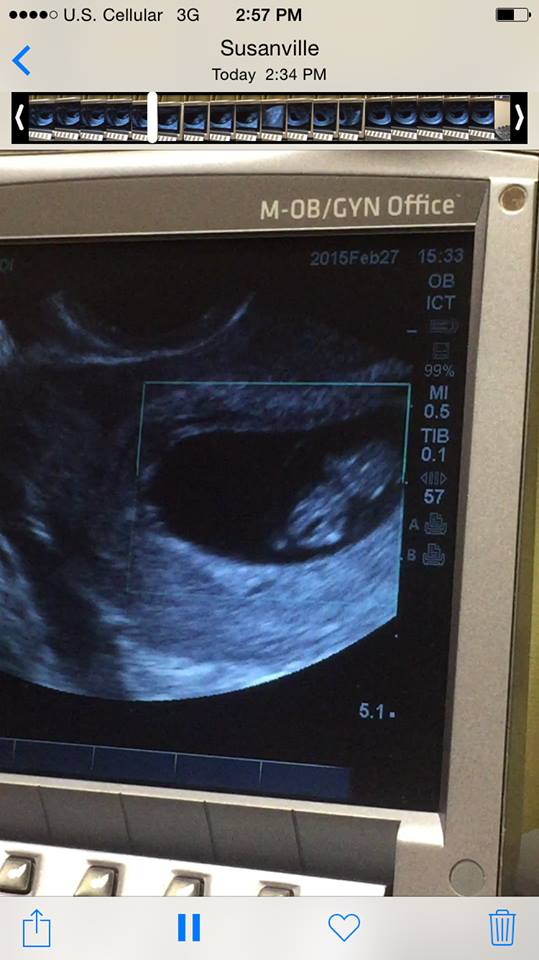

I Have heard of the ramzi theory of the place of the placenta for boy or girl. After two girl on 3 the other 8 months my husband and i decided to try for our boy which will be our last baby...with both my girls we had sex every other day i elevated with my hips under a pillow pointed towards the ceiling did it from behind and i did not orgasm. with this one i only had sex once 12 hours before ovulation stuck baking soda up my you know what orgasmd first did the reverse cowgirl and elevated with my butt in the air since my cervix is towards the front i wanted the semen to fall onto it. the first picture is my first daughter at 12 weeks and the picture is on the abdomen...the second picture is my second daughter at 12 weeks on the abdomen...and the third is the new baby at 8 weeks 4 days through the vagina....any guesses

Attachment 24081Attachment 24082Attachment 24083